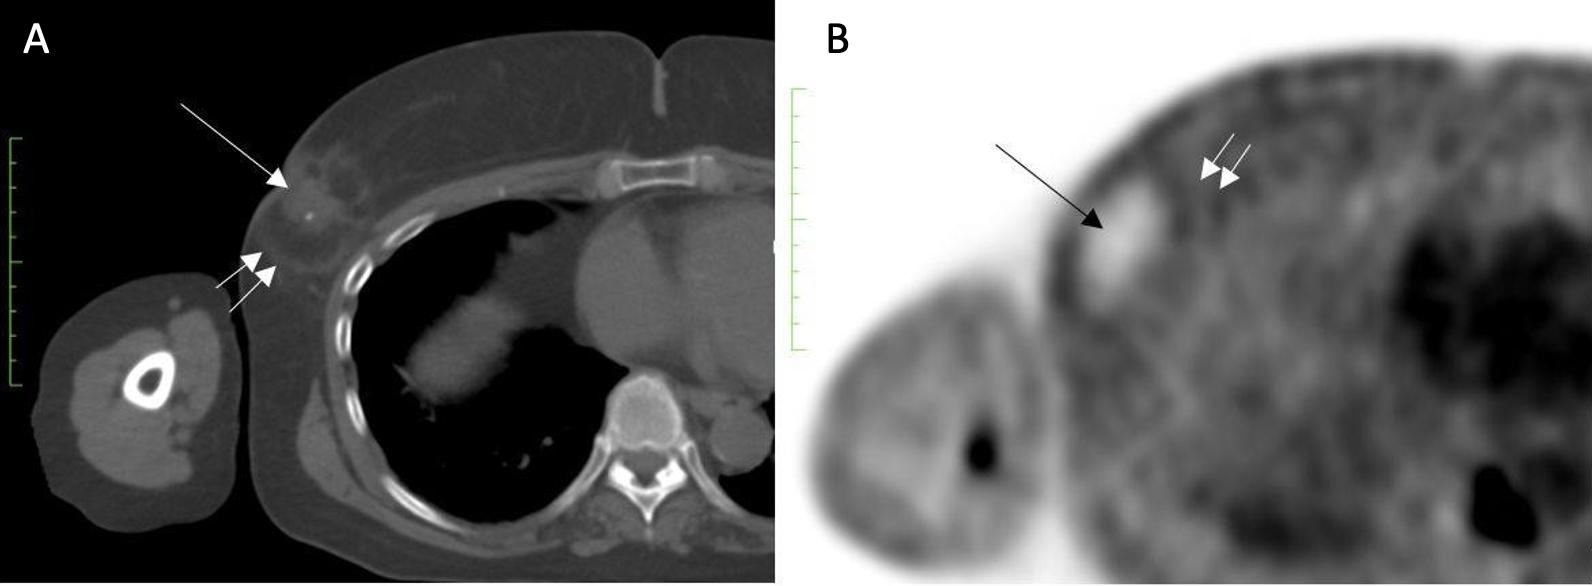

Despite the surgical advancements to minimize the burden of lymph node surgery, some patients with positive lymph nodes continue to refuse lymph node surgery. In the context of patient centered care, some patients with limited nodal disease may be considered for lymph node cryoablation in lieu of surgery (Image 17). Lymph node cryoablation entails several important considerations. Unlike cancers in the breast, the encapsulated nature of lymph nodes obviates the need for cryoablation of a wide surgical margin. Thus, cryoablation freeze times may be cut short when the dimensions of the iceball extend 5 mm beyond the lateral edges of the lymph node. However, lymph node cryoablation is not without hazard. Although lymph node cryoablation is a minimally invasive procedure, the elongated shape of the oval iceball typically causes the cryoablation zone of necrosis to extend 10-15 mm beyond the near and far edges of the lymph node, which can inadvertently cause cryoablation or injury to adjacent nodes, vessels, or nerves. Furthermore, since cryoablation does not permit axillary reverse mapping, lymph node cryoablation, but comparison, is relatively less targeted and potentially more morbid than selectively removal of grossly abnormal axillary lymph nodes.

Image 17. Image A shows grossly abnormal 1.1cm axillary lymph node prior to insertion of cryoprobe. Image B shows abnormal lymph node (outlined with hash marks), cryoprobe traversing the lymph node (white line indicated by arrows), and projection of cryoprobe tip beyond distal end of the lymph node (linear hash marks) prior to beginning first freeze cycle.